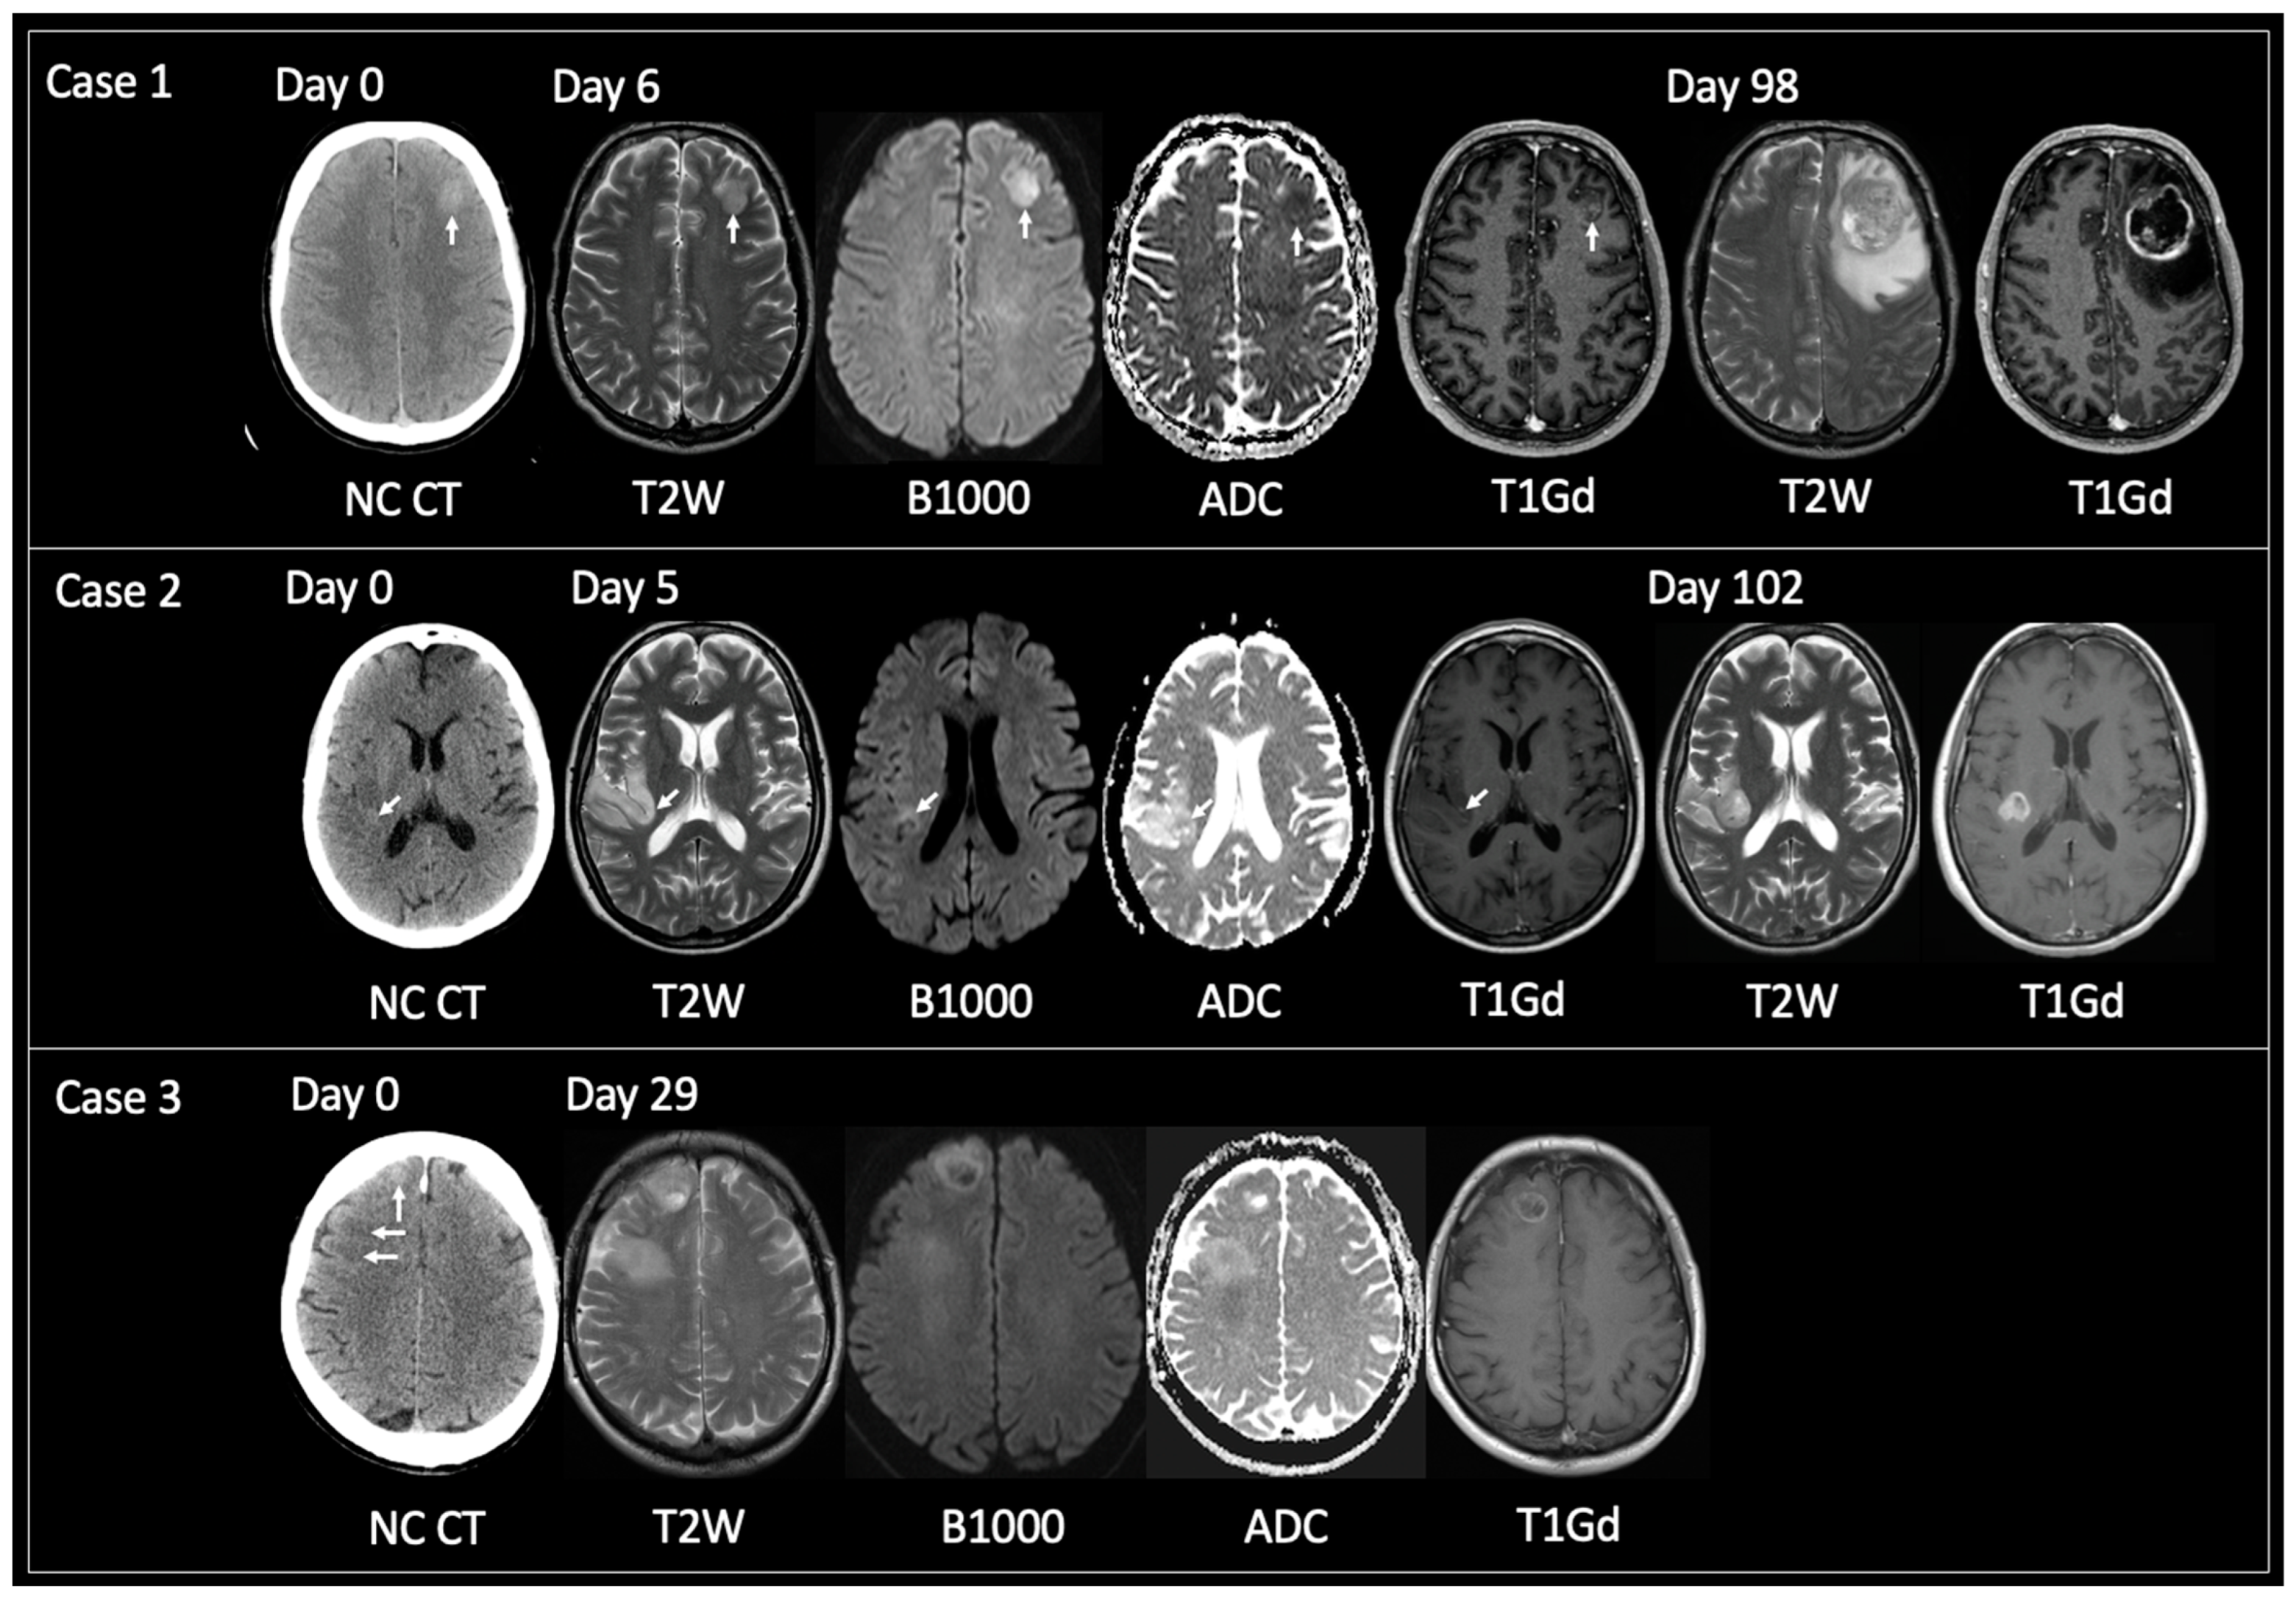

3.1.1. Non-Typical GBM at Time of Tissue Sampling

3.1.2. TRA GBM with Preceding Imaging